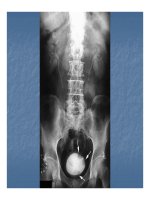

Hình 9. Hình ảnh niệu đồ tĩnh mạch

1.hệ thống đôi không hoàn toàn và hoàn toàn 2. thận

móng ngựa